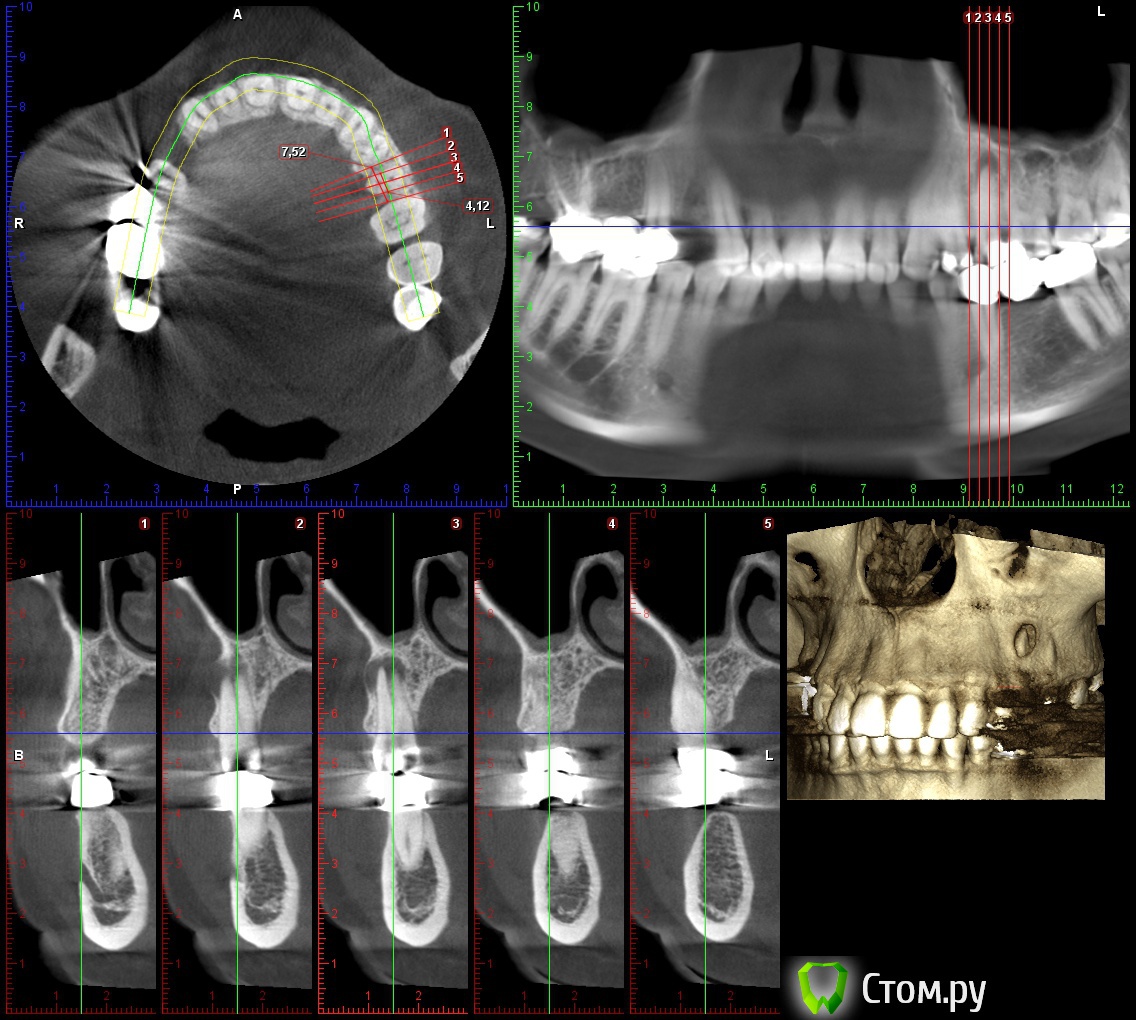

lonely_jack Опубликовано 19 февраля, 2014 Поделиться Опубликовано 19 февраля, 2014 Всем доброго времени суток Принесли КТ для планирования имплантации в области 14 зуба, а там...В области 25 явно напрашивается цистэктомия ( ну и как я думаю удаление 25)... Отсюда пару вопросов:1. Возможность одномоментной имплантации? (естественно с графтом и мембраной)2. Нужно ли на гистологию? (сам думаю, что нет)3. В области 26 и 27 также имеются разрежения (срезы одинаковые, поэтому выкладываю только 26), но с корнями вроде бы не контактируют. Это рисунок кости или все таки стоит насторожиться? Ссылка на комментарий